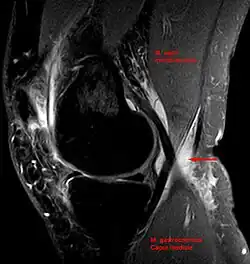

Ultrasound image of Baker's cyst

Diagnosis is by examination. A Baker's cyst is easier to see from behind with the patient standing with knees fully extended. It is most easily palpated (felt) with the knee partially flexed. Diagnosis is confirmed by ultrasonography, although if needed and there is no suspicion of a popliteal artery aneurysm then aspiration of synovial fluid from the cyst may be undertaken with care. An MRI image can reveal presence of a Baker's cyst.